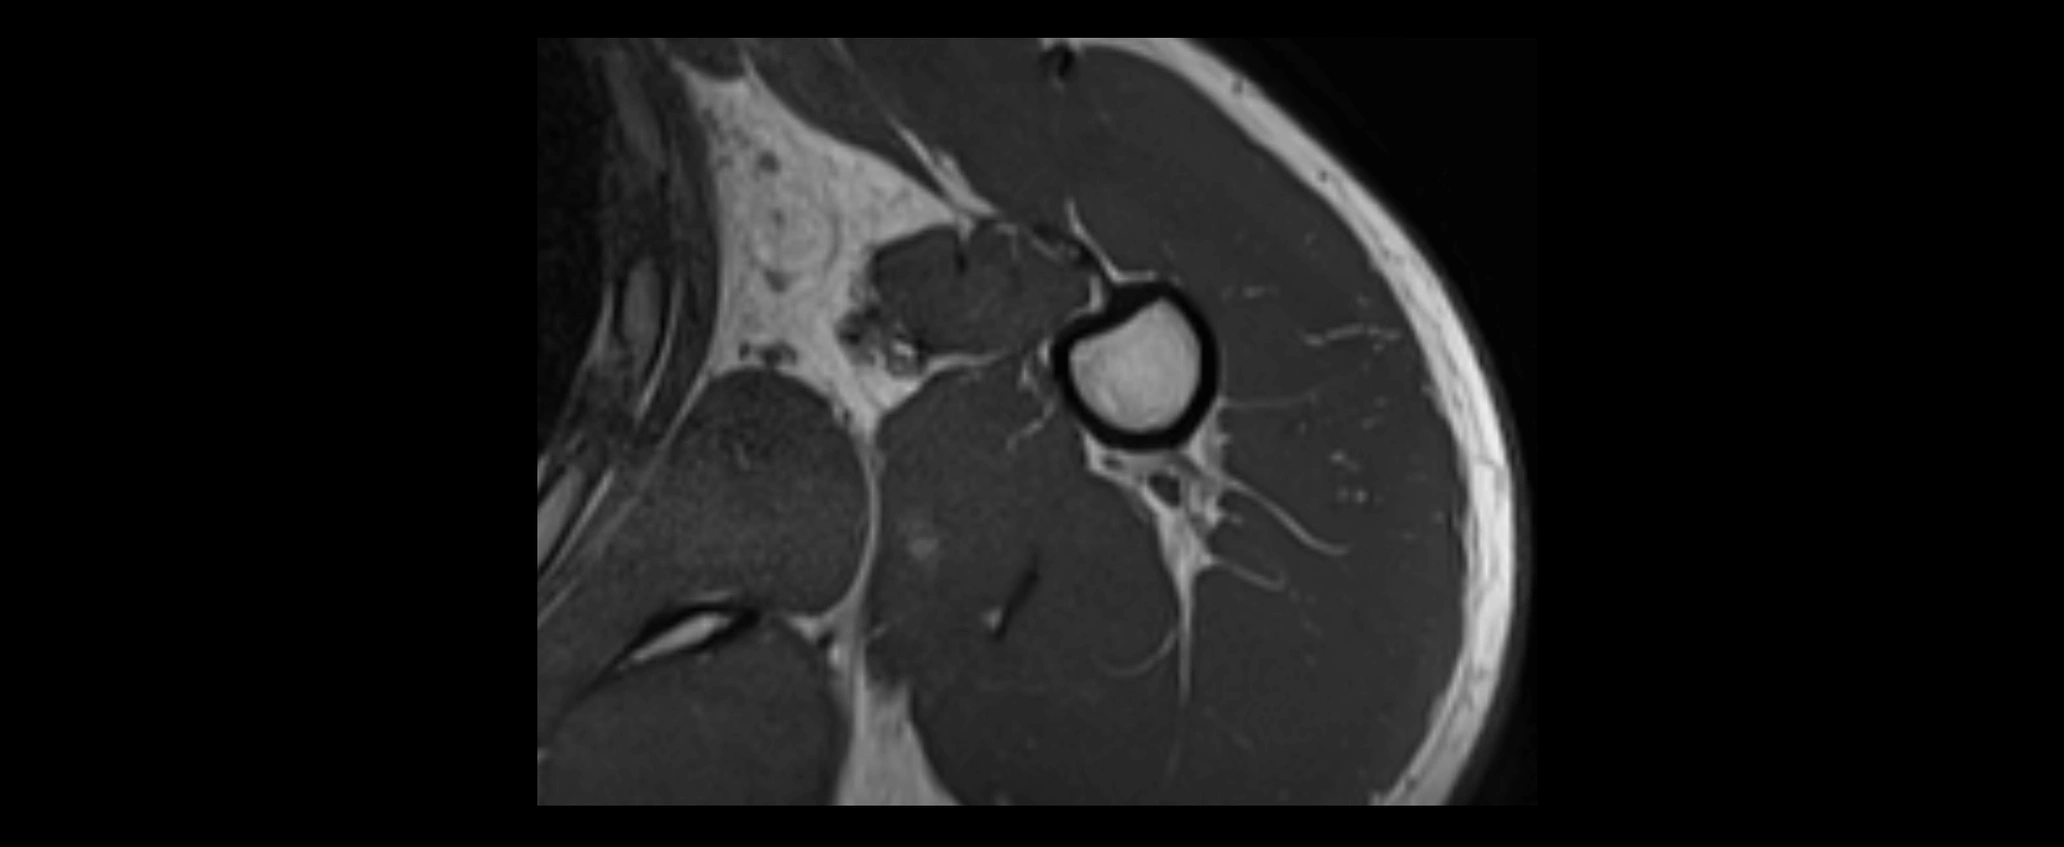

MRI images

image